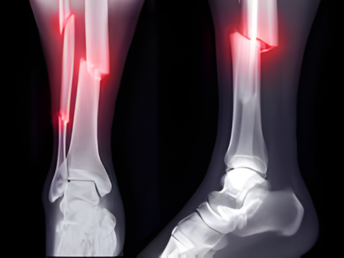

Fractures

02. Trauma care and fracture management.

Expert treatment for fractures, injuries, and accidental trauma to ensure proper healing and full functional recovery.